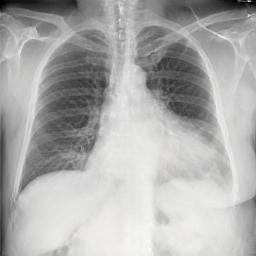

To address these issues, we propose a novel Adaptive patch-word Matching (AdaMatch) model to correlate chest X-ray (CXR) image regions with words in medical reports and apply it to CXR-report generation to provide explainability for the generation process. AdaMatch exploits the fine-grained relation between adaptive patches and words to provide explanations of specific image regions with corresponding words. To capture the abnormal regions of varying sizes and positions, we introduce the Adaptive Patch extraction (AdaPatch) module to acquire the adaptive patches for these regions adaptively. In order to provide explicit explainability for CXR-report generation task, we propose an AdaMatch-based bidirectional large language model for Cyclic CXR-report generation (AdaMatch-Cyclic). It employs the AdaMatch to obtain the keywords for CXR images and `keypatches' for medical reports as hints to guide CXR-report generation. Extensive experiments on two publicly available CXR datasets prove the effectiveness of our method and its superior performance to existing methods.